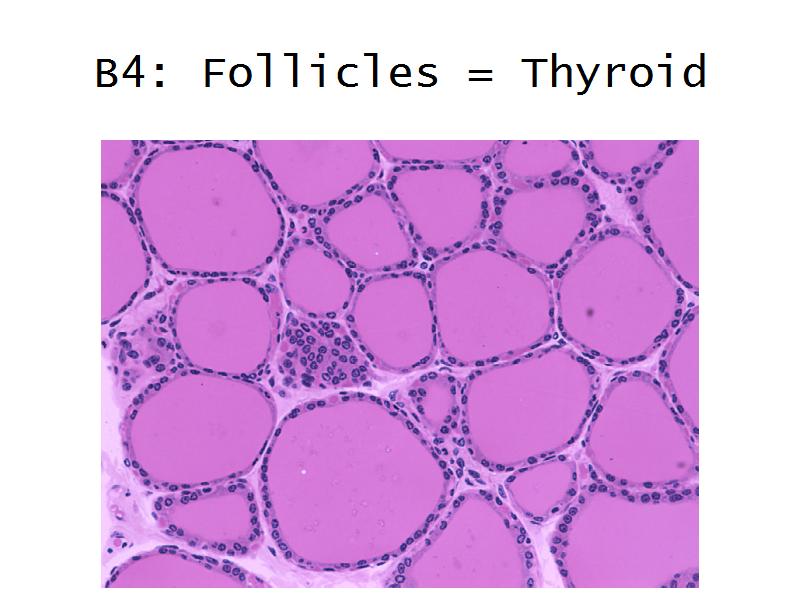

Thyroid gland

Four elements making up the thyroid

Thyroid gland

- Follicle

- Follicular epithelium

- Parafollicular cells

- Colloid

- Identify them on the next slide